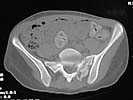

I did as suggested, I performed a 2-stage procedure (posterior sacral osteotomy and anterior take-down of left-sided rami fractures and anterior plate and percutaneous iliosacral screw fixation). It was a difficult and humbling experience. I felt as though the sacral osteotomy was complete and seemed so using intraoperative image views (inlet, outlet and true lateral of the sacrum) however after placing the distractor anteriorly I found that I could not see the sacrum well due to the bulk of the distractor itself. I then replaced it with radiolucent external fixation bars and noted widening of the left anterior SI joint.

Apparently my sacral osteotomy was not complete and the rotational correction (lateral and inferior) was occurring through the SI joint, at least anteriorly. An intraoperative x-ray showed definite improvement of the leg length discrepancy but not complete. I felt that in addition to the rotational correction the left hemipelvis also needed to move inferior as well. Due to the patient's small size, traction on her left leg simply produced pelvic obliquity and I really did not have a way of placing well leg traction which would require a post and at the same time obtain adequate intraoperative image views. Long and the short is I accepted a less than perfect reduction but with leg lengths now with less than 1 cm difference clinically and radiographically and I fused her left SI joint. No post-op nerve deficits. It was definitely a learning experience.

Any and all feed back is appreciated. Postop pics enclosed.

Probably the best treatment is avoiding this situation. Educate the individuals involved in her initial evaluation. Teach them the importance of clinical and radiographic patient evaluations. Teach them exactly how to examine an injured pelvis. If it had been examined initially, the clinical instability would have been obvious. The radiographs reveal bilateral, comminuted, displaced anterior ramus fractures along with a sacral fracture which violates the anterior, middle, and posterior portions of the sacrum (analogous to a complete sacroiliac dissociation)....a "3 column injury"(if you pretend that the sacrum is a vertebra), so to speak.

Intraoperative fluoro can be misleading regarding deformity corrections...maybe consider plain films when needed. Notice this lady's external rotation of the left hemipelvis postop and its impact on the acetabular coverage...see the inlet(caudal) view with attention to the ischial spine assymetry.